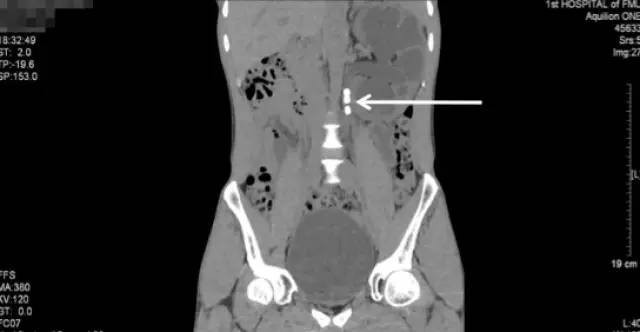

白色箭头所指就是引起梗阻的掉到输尿管的结石

CT三维重建图像可见左肾明显增大、扩张积水、多发结石

由于该病例结石较多而且分散,肾内结构复杂,所以我们在入院后很快为柯先生安排了全麻微创手术“左侧经皮肾镜碎石取石术(双通道)+左肾造瘘+左输尿管支架置入术”,(经皮肾镜取石术是指:在B超或X线精准定位下,在患者的皮肤和肾脏之间建立一条通道,采用碎石设备通过这条通道将肾内的结石碎裂后再由这一通道取出。)手术顺利,耗时1个半小时。

手术前KUB

术后复查KUB

通过本次术前术后的KUB对比,可以看到,经过这次手术,柯先生左肾的大部分结石已经消失了,仅剩下盏的一些小的结石。